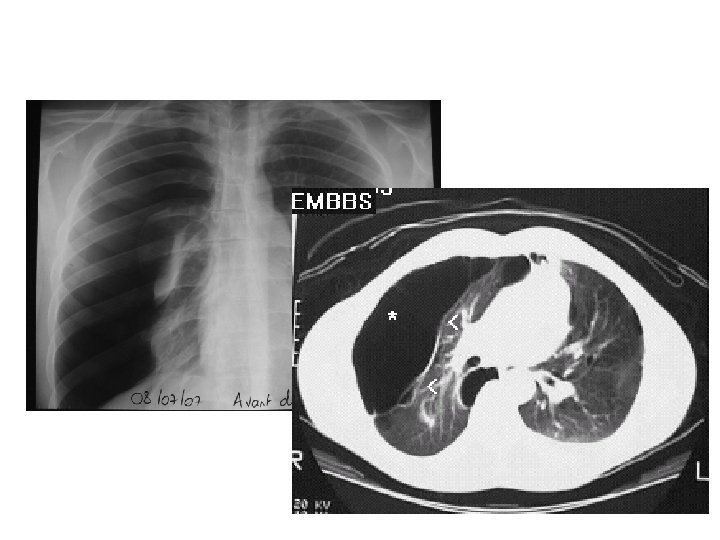

Pleurésie modérée